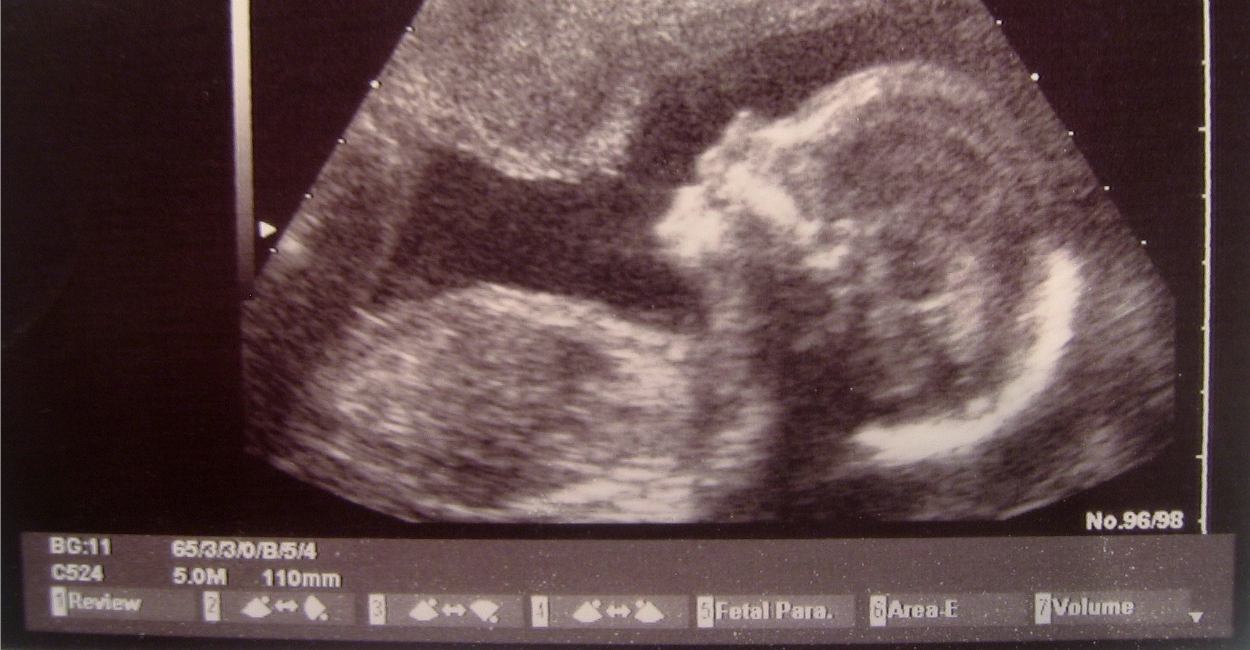

A bill has been introduced in the Ohio legislature that would prohibit abortion based on a fetal diagnosis of Down syndrome.

House Bill 135, titled “The Down Syndrome Non-Discrimination Act,” would prohibit abortion because of “a prenatal diagnosis of Down syndrome in an unborn child.”

According to the Charlotte Lozier Institute, a pro-life research organization, several studies show that the abortion rate for pregnancies with a Down syndrome diagnosis can range from 61 percent to 93 percent, depending on factors such as income level and religious beliefs.

About 6,000 babies with Down syndrome are born each year in the United States.